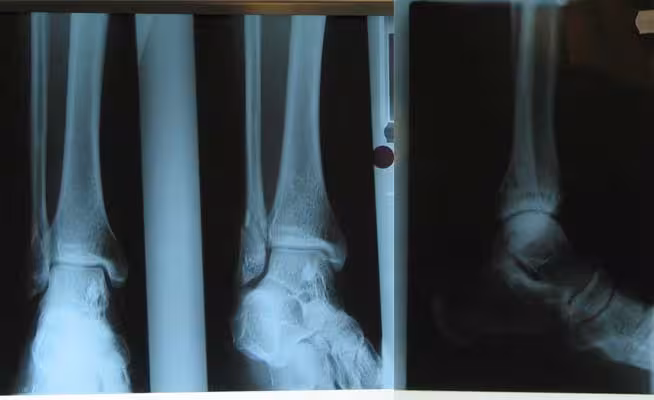

Yeah, yeah I know. Who breaks their leg playing badminton? You can see a spiral fracture of my fibula down near my ankle.

Broken leg X-ray